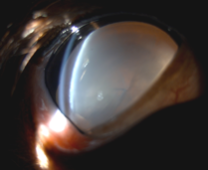

​정확한 진단을 위해 세극등검사 및 안구초음파 검사를 진행하였습니다. 이를 통해 수정체 탈구 증상과, 성숙단계의 백내장을 진단하였습니다.

✔️수정체 탈구(lens luxation)

– 수정체가 정상 위치에서 이탈된 상태

세극등 검사를 통한 수정체 위치 이상 확인

세극등 검사에서 각막과 수정체가 가까워짐 / 출처: 에스동물메디컬센터